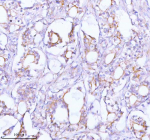

Immunohistochemical staining of TNIK using anti-TNIK antibody. TNIK was detected in a paraffin-embedded section of human prostate adenocarcinoma tissue. Heat mediated antigen retrieval was performed in EDTA buffer (pH 8.0, epitope retrieval solution). The tissue section was blocked with 10% goat serum. The tissue section was then incubated with 2 ug/ml rabbit anti-TNIK antibody overnight at 4oC. Peroxidase Conjugated Goat Anti-rabbit IgG was used as secondary antibody and incubated for 30 minutes at 37oC. The tissue section was developed using an HRP secondary and DAB substrate.